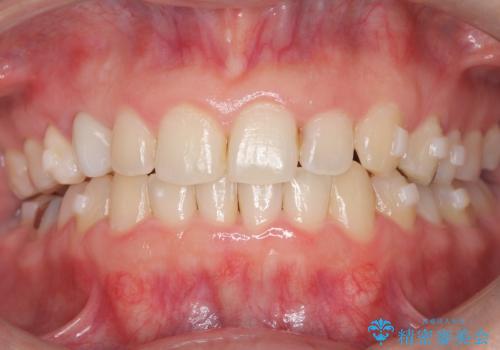

- 下の歯のがたつき(叢生)、真ん中(正中)が右にずれていることを主訴に来院されました。右上前から3番目の永久歯が埋まっている(埋伏)していることから正中は可能な限り合わせることをゴールとしてマウスピースでの矯正治療を選択しました。

今回の矯正治療では、透明なマウスピース型の装置インビザラインを使用しました。がたつきをとるため、安全性が確保できる範囲で歯と歯の間を少し削り必要なスペースを確保しました。